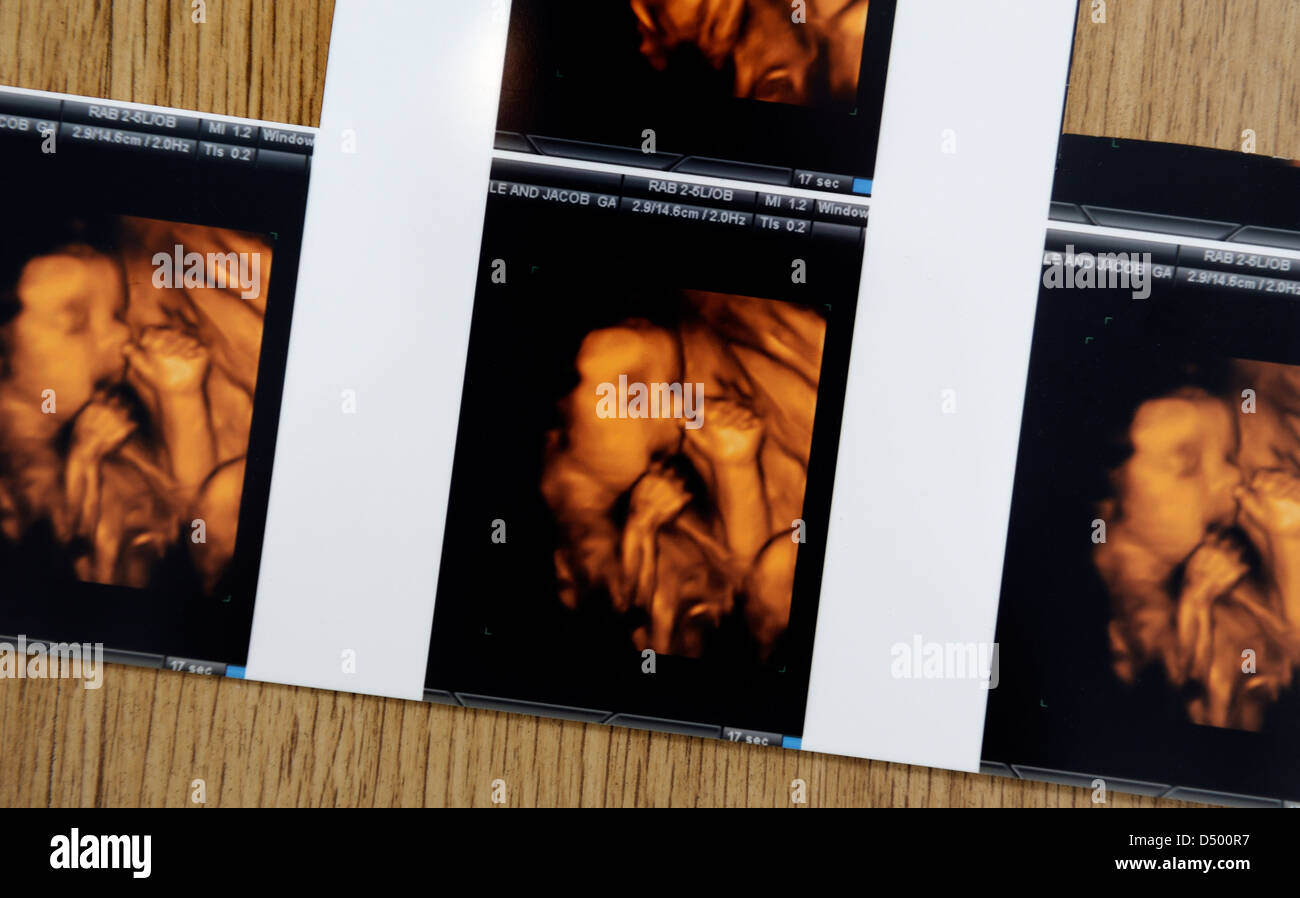

4D bambino scansioni Foto Stockhttps://www.alamy.it/image-license-details/?v=1https://www.alamy.it/foto-immagine-4d-bambino-scansioni-54705035.html

4D bambino scansioni Foto Stockhttps://www.alamy.it/image-license-details/?v=1https://www.alamy.it/foto-immagine-4d-bambino-scansioni-54705035.htmlRMD500R7–4D bambino scansioni